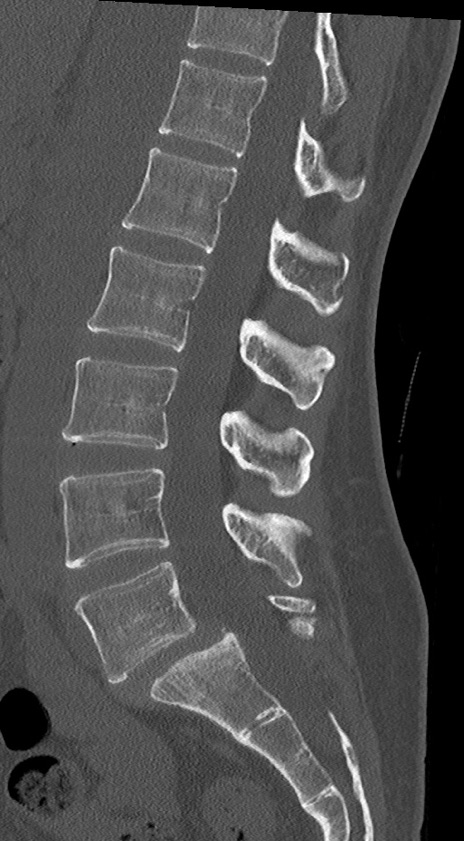

【整形】TIPS症例4 腰椎CT(矢状断像)

腰椎CT